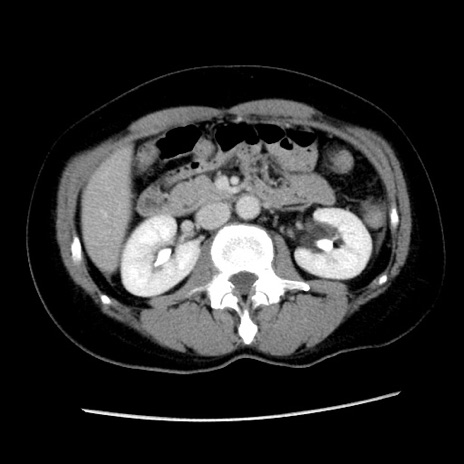

矢状断像

症例10(横断像)

【症例】 50歳代女性

【主訴】 腹痛

【現病歴】前日生レバーを食べた。今朝に排便あり。 昼前に突然発症の腹痛を生じ、当院救急外来を受診した。

【身体所見】 意識清明、腹部:平坦、軟、下腹部やや左を中心に圧痛・反跳痛あり、筋性防御あり

【データ】WBC 7800、CRP 0.07